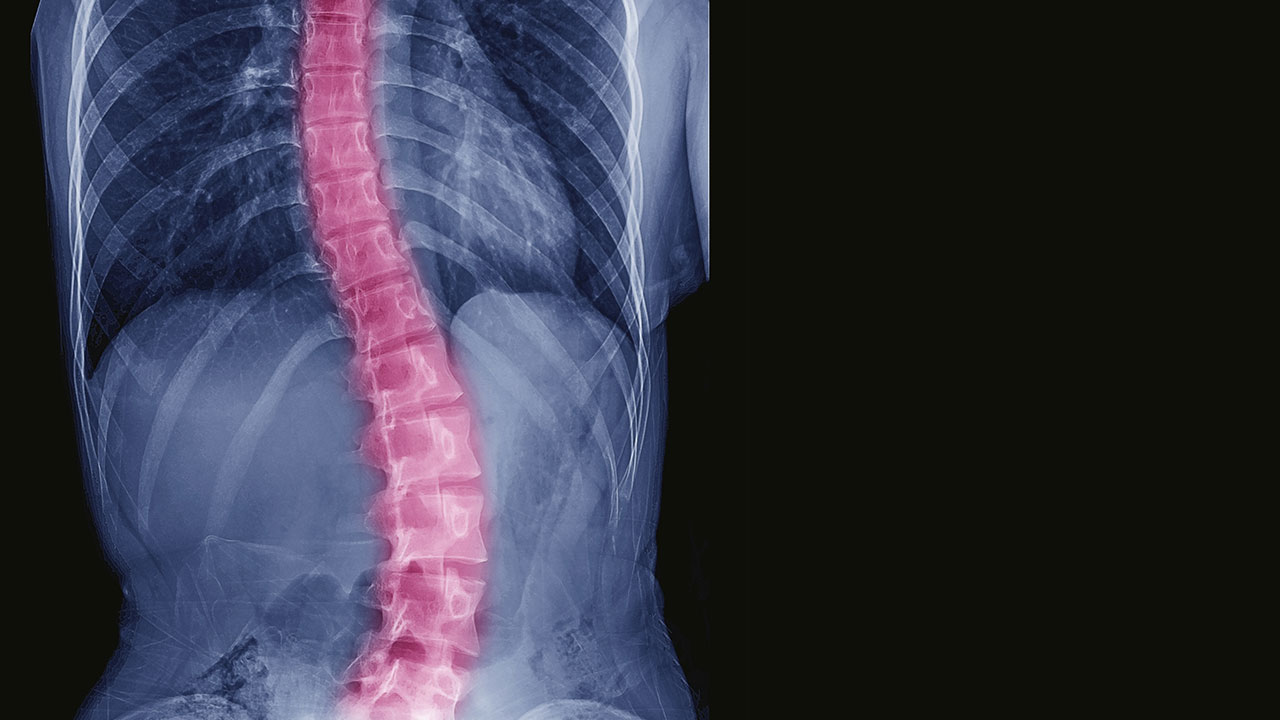

Adolescent idiopathic scoliosis (AIS) impacts 2% to 3% of healthy 10 to 18-year-olds and is responsible for more than $3 billion in annual public health costs. Despite its prevalence and high genetic heritability, it’s not clear which children are at risk for AIS, and among those diagnosed, who are more likely to have significant curve progression. While several genetic variants potentially associated with a predisposition to AIS have been identified, the exact mechanism underlying its pathology is not understood and clinical translation of these variants has not advanced.